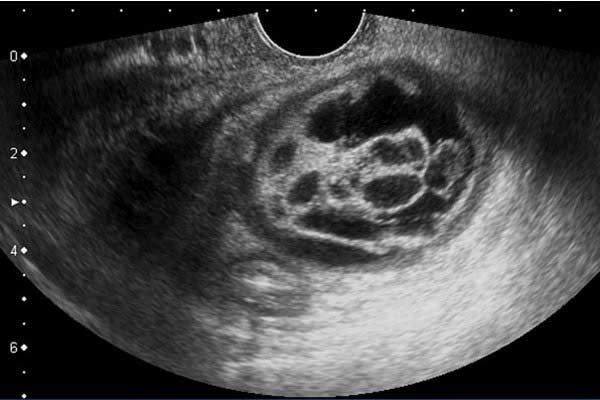

راه های تشخیص کیست تخمدان در دختران

از آن جایی که تشخیص کیست تخمدان اصلی ترین مرحله برای درمان آن هاست باید پزشک آزمایشاتی تجویز کند و به وسیله آن را کیست تخمدان را تشخیص دهد. انجام برخی از آزمایشات در دختران و زنانی که به کیست تخمدان مبتلا هستند می تواند در تشخیص آن موثر باشد. از جمله این آزمایشات می توان به لاپاراسکوپی، سونوگرافی لگنی، ام آر آی، آزمایش خون CA 125 و سی تی اسکن اشاره کرد.